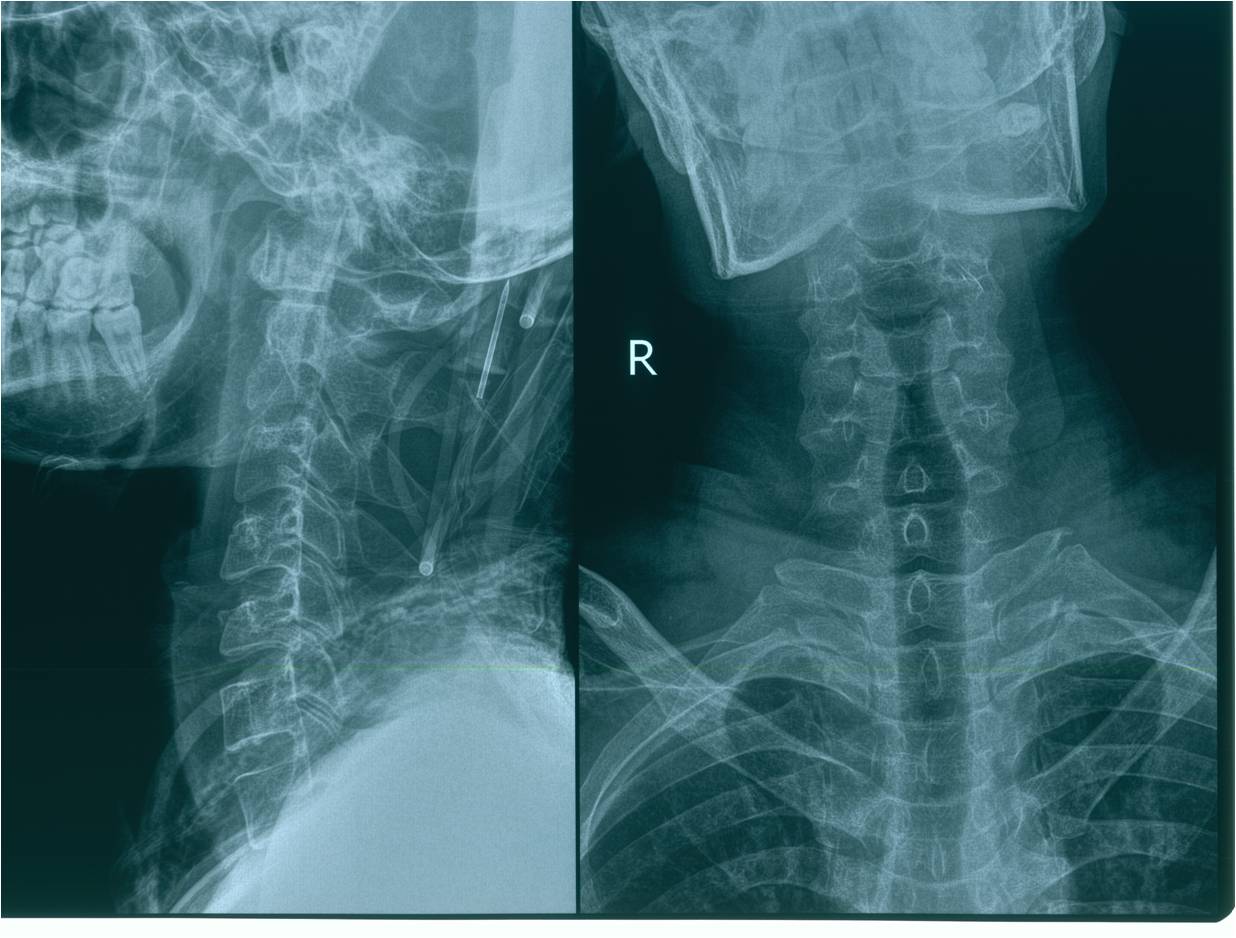

2012-11-18 车祸致四肢感觉、运动及二便功能障碍。

查体:意识清楚,呼吸均匀,查体合作。双侧感觉平面颈4,运动平面颈5. 颈6以下轻触觉保留至肛周,针刺觉消失。颈5以下只有肛门括约肌保留运动功能。下肢肌张力0级。腱反射消失。球海绵体反射可引出。当地医院行X片、CT、MRI检查